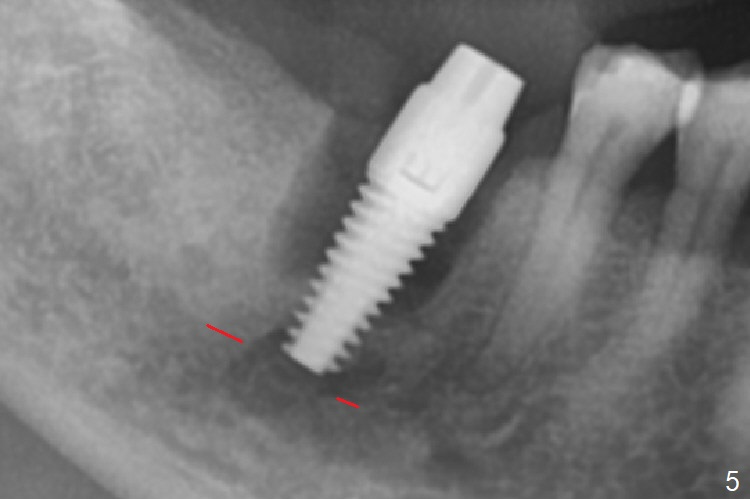

After extraction of the tooth #30 and curettage, the septum becomes so thin that the most coronal portion has to be removed with Rongeur and surgical fissure bur (bone height reduction). Initial osteotomy depth is ~ 4 mm from the flattened septum (Fig.1 (yellow dashed line: apical end of the osteotomy)). Following sequential osteotomy (with intact osteotomy wall), a 6x17 mm tap is placed with apparent clearance from the Inferior Alveolar Canal (Fig.2). When the same size implant is placed with 60 Ncm (Fig.3), the nervous patient feels that the implant is too long (causing pain). CT (Fig.4) and panoramic X-ray (Fig.5) show limited clearance (1.4 mm), but compression of the canal due to high torque could not be ruled out. Since limited amount of the native bone (4.1 mm) for primary stability, the implant is not backed up immediately. Vanilla graft is placed after fabrication of an immediate provisional (Fig.6 *). In brief, immediate implant should be avoided when the septum is thin or the native bone is less than 5 mm (3 mm for primary stability; 2 mm for clearance). In fact the implant has to be untorqued 4-5 times of turn to relieve pain nearly 1 month postop. The patient returns for impression 5 months postop (4 months post implant back up, Fig.7). When the abutment is changed to 5x5 mm and prepared, she reports earache (residual nerve damage?). The patient has had the similar complaint 9 months postop; it appears that there is radiolucency distally (Fig.8 >, as compared to radiopaque mesially (*)). The distal gingiva is tender. With a remade permanent crown, oral hygiene instruction is provided. If necessary, CBCT is taken with possible bone graft.